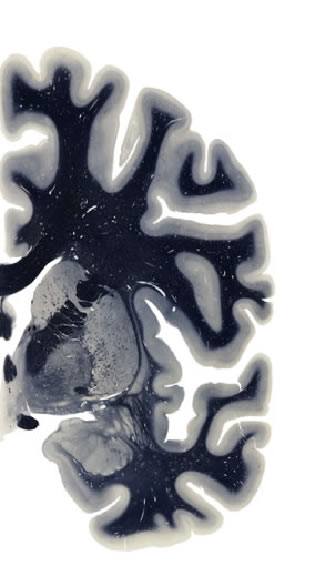

Hi-Resolution Sections · Cells (Nissl Staining) · Virtual Microscopy

Frontal sections (Nissl) from the Atlas Brain:

Slice ID:

r3-1307

Plate NR:

ca 24

Position:

2,5 mm